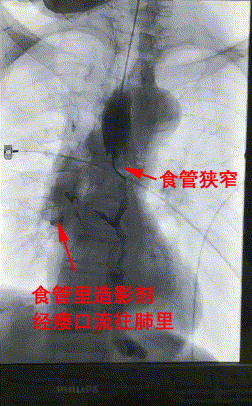

3月28日上午,楊阿姨被送進了介入手術室,李旭丹主任等專家根據術前方案上台施術,先采用飛利浦DSA開展食道造影,明确食道狹窄端及瘘口位置,後經導絲引入食管支架釋放于準确位置。DSA顯示支架成功擴張食管狹窄端并封閉瘘口,順利完成手術。

△術前DSA造影顯示:食管狹窄+食管氣管瘘。